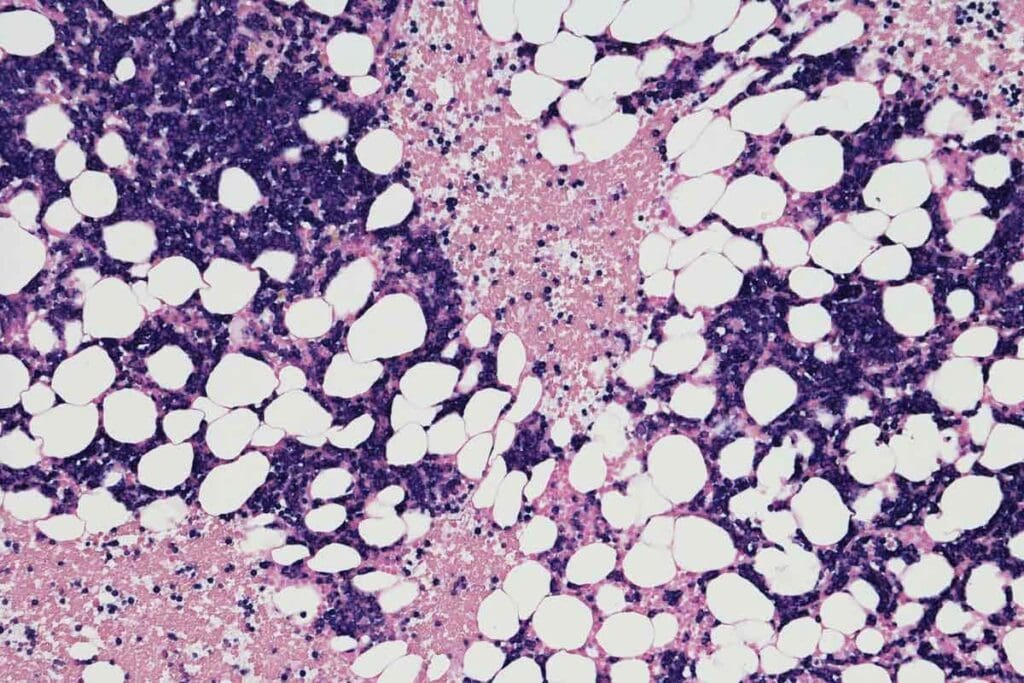

The Biology of Bone Marrow and Blood Cell Formation

Bone marrow is key in making blood cells. When myelosuppression happens, it messes with this process. Knowing how bone marrow works helps us understand the impact of this condition.

Anatomy and Function of Bone Marrow

The bone marrow is inside the bones. It makes hematopoiesis, or blood cells. Stem cells in the marrow turn into different blood cells, like red and white blood cells, and platelets.

Hematopoiesis: The Process of Blood Cell Creation

Hematopoiesis is a complex process. It involves stem cells growing and changing into blood cells. This is vital for keeping the right number of blood cells in our body.

How Myelosuppression Disrupts Normal Blood Cell Development

Myelosuppression messes with hematopoiesis. This leads to fewer blood cells being made. This can cause anemia, neutropenia, and thrombocytopenia. Patients then face more risks of infections and bleeding.